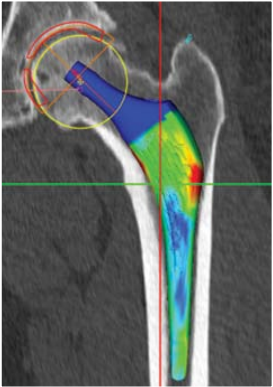

Les nouvelles approches de planification 3D dans le cadre de la mise en place d’une Prothèse Totale de Hanche permettent d’anticiper ces particularités individuelles au cas par cas.

Cette planification est réalisée à partir d’un scanner de votre hanche que votre médecin vous aura prescrit quelques semaines avant l’intervention. Cet examen permet de retranscrire votre anatomie en 3 dimension de manière extrêmement fidèle.

Réalisé avant votre intervention, la planification 3D a pour but d’anticiper les éventuels problèmes liés aux particularités de chacun et permet donc de visualiser et fiabiliser la procédure chirurgicale. Durant votre intervention chirurgicale Cette approche nouvelle permet une mise en place au plus juste des implants de votre Prothèse Totale de Hanche.